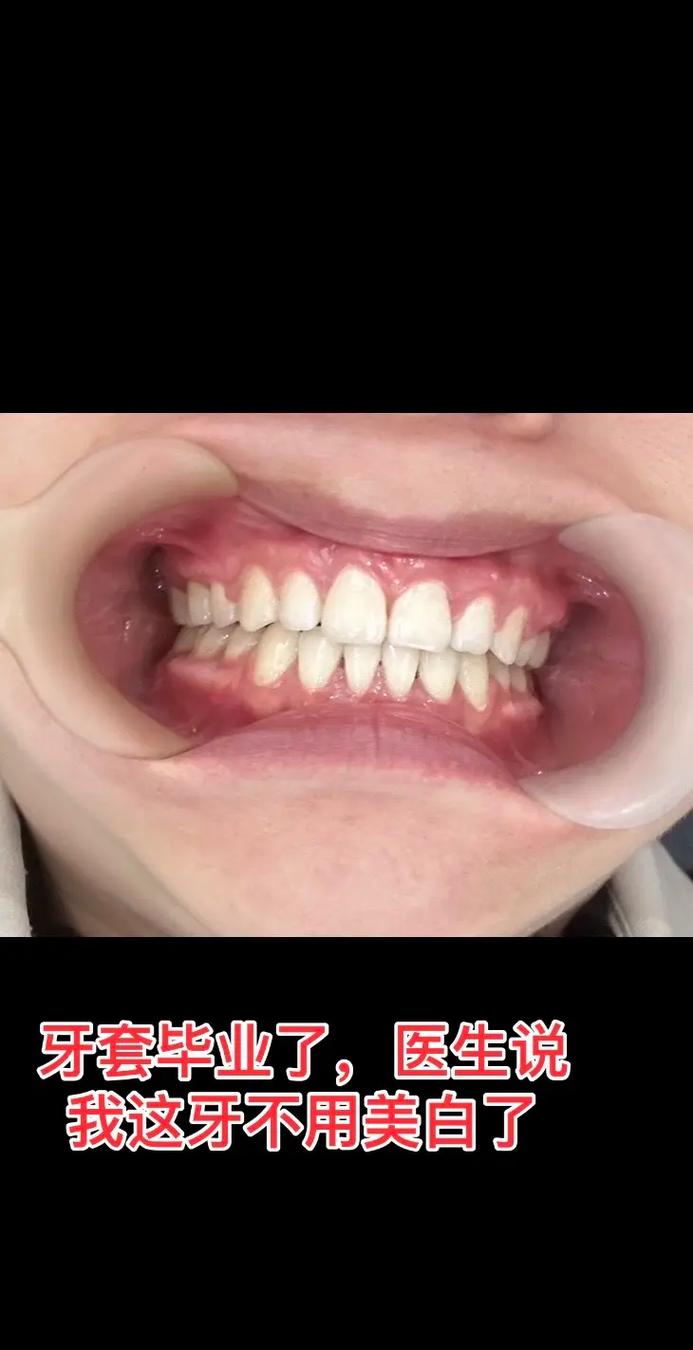

(图片来源网络,侵删) -